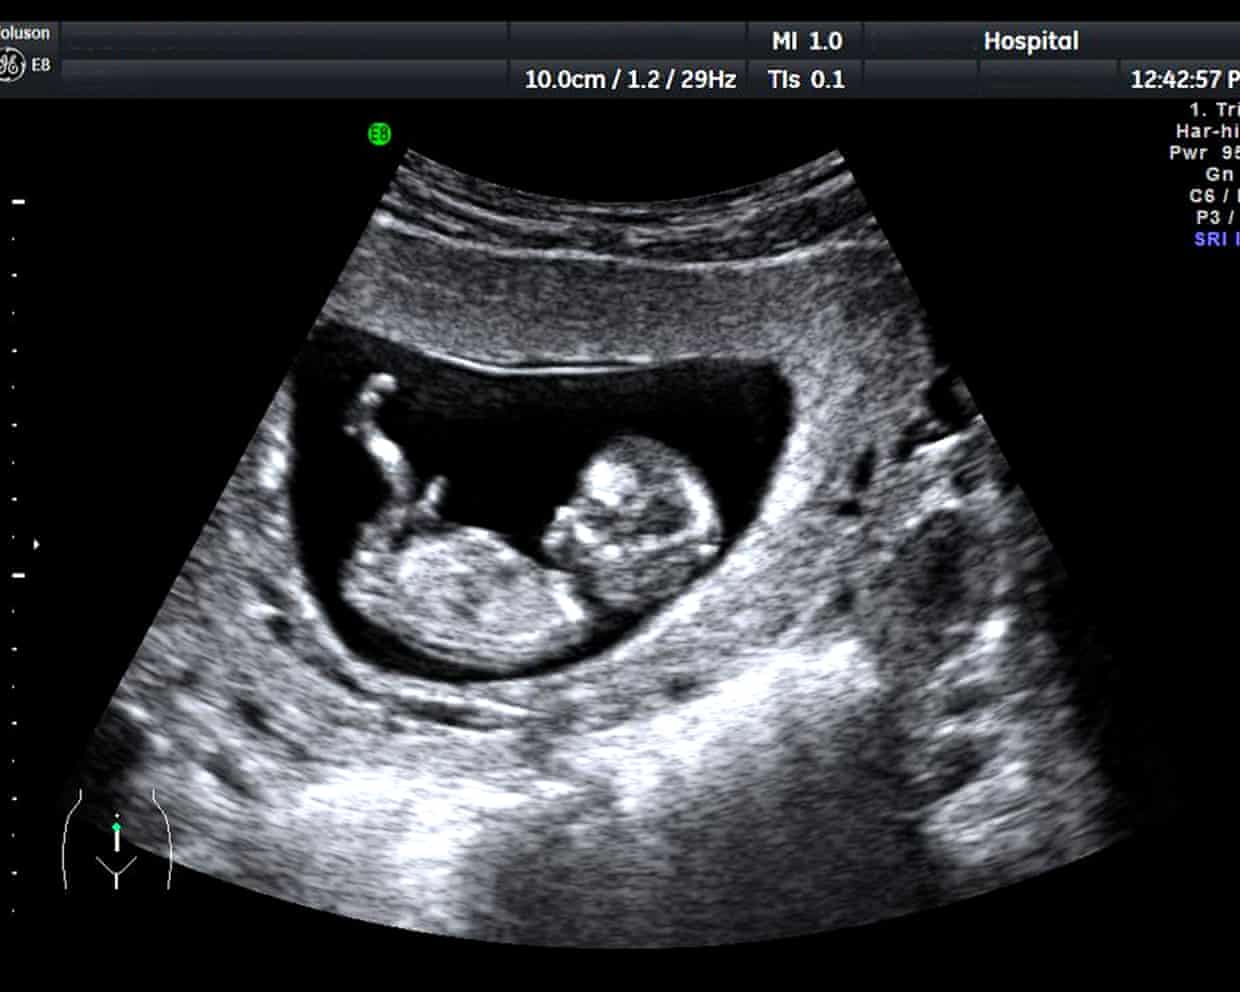

UK’s unregulated pregnancy scan clinics putting lives in danger, say experts

High street clinics offering pregnancy scans could be putting unborn babies and their mothers in danger through a lack of properly trained staff, UK experts have warned.According to the Society for Radiographers (SoR), high street clinics have seen a huge growth in numbers. However, hospital specialists say they have seen cases of missed health problems, misdiagnosed conditions, and situations in which women were erroneously told their babies were malformed or had died.“I had a lady referred for a potential miscarriage from a clinic and when I scanned her they’d measured a bleed in the womb and they completely missed a very early pregnancy sac with a baby inside it,” said Katie Thompson, a hospital sonographer and president of the SoR.“Potentially, if they were at a private clinic that could offer a miscarriage service, then they could have been given some medication to bring on a miscarriage on a pregnancy that was actually not miscarrying,” she said